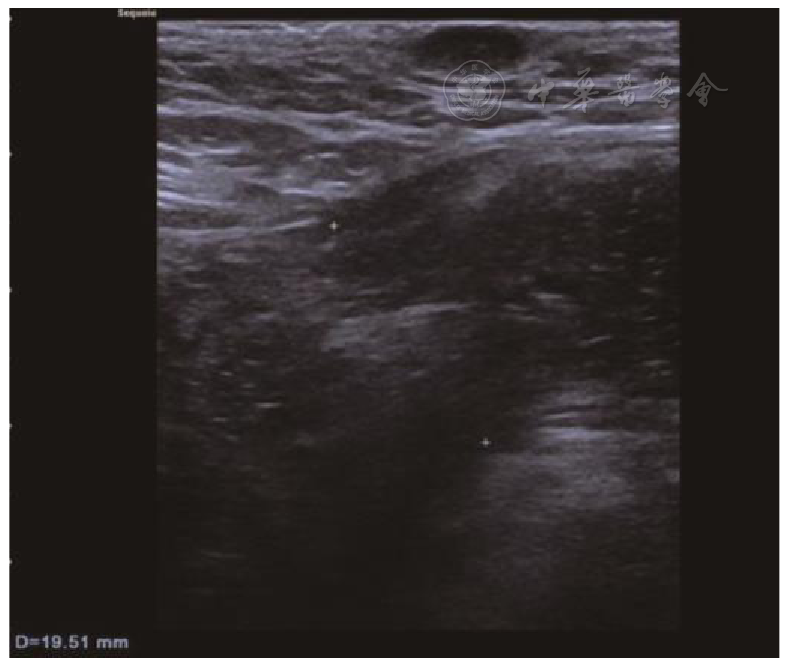

The sensitivity and specificity of MSCT in diagnosing inguinal hernias were 97.79% and 80.00%, respectively, with a kappa value of 0.652. The sensitivity and specificity of high-frequency ultrasound in diagnosing inguinal hernias were 96.32% and 80.00%, respectively, with a kappa value of 0.551. For the diagnosis of indirect hernias, MSCT had a sensitivity of 97.00% and a specificity of 94.44%, with a kappa value of 0.906; for the diagnosis of direct hernias, MSCT had a sensitivity of 94.44% and a specificity of 97.00%, with a kappa value of 0.906. High-frequency ultrasound had a sensitivity of 92.00% and a specificity of 88.89% for diagnosing indirect hernias, with a kappa value of 0.781, and a sensitivity of 88.89% and a specificity of 92.00% for diagnosing direct hernias, with a kappa value of 0.781. Indirect inguinal hernias presented with mixed density or were cystic-solid, all distributed on the anterior side of the inguinal ligament and lateral to the inferior epigastric artery, without a crescent sign or filling of the femoral triangle. Direct hernias were all distributed on the anterior side of the inguinal ligament and medial to the inferior epigastric artery, without filling of the femoral triangle, and often with a lateral crescent sign. The indirect hernia sac was located lateral to the origin of the inferior epigastric artery, and the diameter and shape of the hernia ring varied greatly. The direct hernia sac was located medial to the inferior epigastric artery, with no significant changes in the local abdominal wall, clear intestinal wall layers, no obvious hernia sac neck, and a small amount of fluid dark area could be detected in the hernia sac cavity of some patients. The hernia ring was located medial to the inferior epigastric vessels, and there was a small amount of color blood flow signal in the intestinal wall. The proportions of contents in indirect hernias were, in descending order: intestinal canal, greater omentum, ovary, effusion, intra-abdominal fat, and bladder. The proportions of contents in direct hernias were, in descending order: intestinal canal, intra-abdominal fat, greater omentum, effusion, ovary, fat, and bladder. After Bonferroni correction (corrected significance level of P<0.0083), there were no statistically significant differences in the detection rates of all contents between the two groups (all P>0.0083).